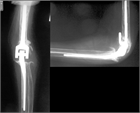

1. 投薬治療抵抗性のリウマチ肘では関節破壊が軽度の場合、滑膜切除術が勧められる(推奨度2)

1. 関節破壊が高度の場合、人工肘関節形成術が勧められる(推奨度3)。ただし、手術手技、後療法に習熟した施設、術者によって行われることが望ましい。